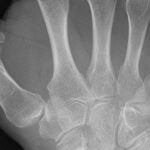

This hub outlines “7 Uses of Gadolinium,” highlighting its major applications—from MRI contrast agents and high-strength magnets to alloys, phosphors, and nuclear uses. Each numbered use links to a detailed article covering how it works, real-world examples, benefits, and safety considerations for students, researchers, and professionals.